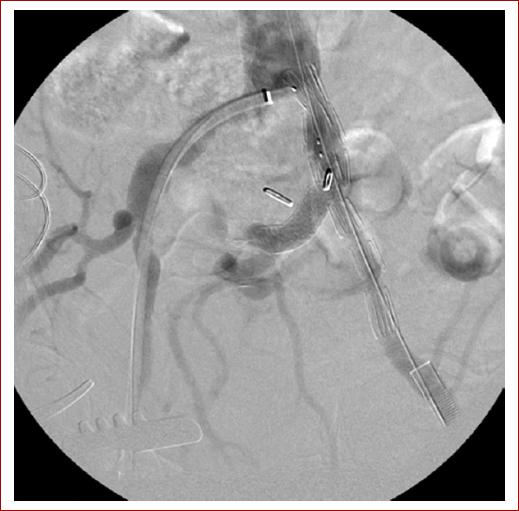

A pesar de que no existen ensayos aleatorizados que comparen la reparación endovascular ilíaca (REVI) (Fig. 4) vs. la reparación abierta, Zhorsel et al. (2019) concluyen que los AAI pueden tratarse de forma segura y eficaz con REVI o reparación abierta en cuanto a morbilidad, mortalidad y supervivencia a largo plazo a los 30 días, aunque la ausencia de reintervención es significativamente menor después de REVI16,17.

Figura 4 Reparación de aneurisma de la arteria ilíaca común con un dispositivo de endoinjerto ramificado ilíaco. La endoprótesis se extiende hacia las arterias ilíacas interna y externa (tomada de Perini et al., 202120)